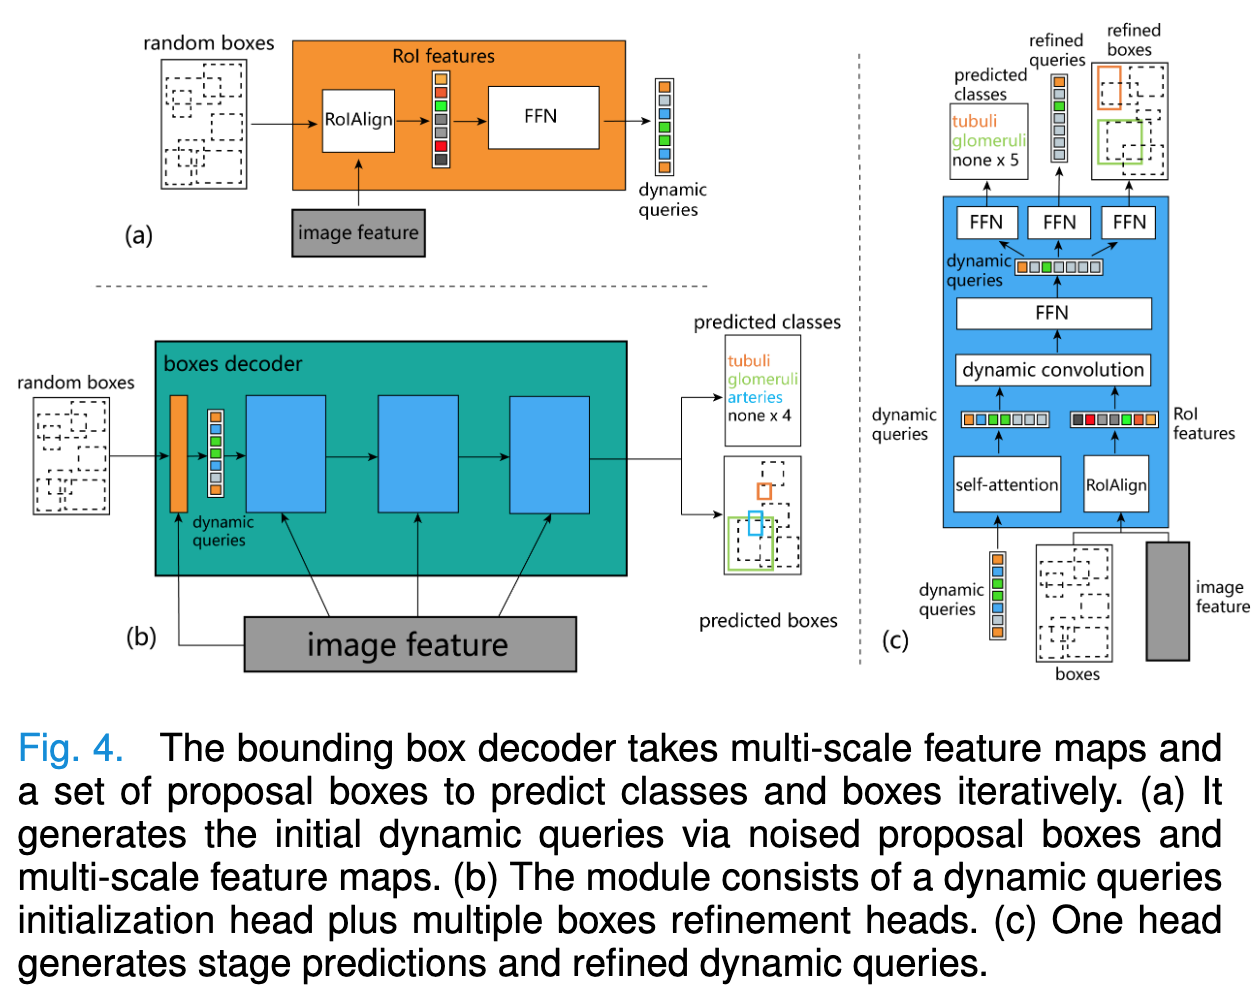

📚肾脏活检结构模型, (from 荷兰莱顿大学)

| Advances in Kidney Biopsy Structural Assessment through Dense Instance Segmentation Authors Zhan Xiong, Junling He, Pieter Valkema, Tri Q. Nguyen, Maarten Naesens, Jesper Kers, Fons J. Verbeek 肾活检是诊断肾脏疾病的金标准。肾脏病理学家专家做出的病变评分是半定量的,并且观察者之间的变异性很高。因此,自动获取每个分割的解剖对象的统计数据可以在减少劳动力和观察者之间的变异性方面带来显着的好处。然而,活检的实例分割一直是一个具有挑战性的问题,因为a平均有大约300到1000个密集接触的解剖结构,b具有至少3个的多个类,c具有不同的尺寸和形状。当前使用的实例分割模型无法以有效且通用的方式同时应对这些挑战。在本文中,我们提出了第一个无锚实例分割模型,该模型结合了扩散模型、变压器模块和 RCNN 区域卷积神经网络。我们的模型仅在一台 NVIDIA GeForce RTX 3090 GPU 上进行训练,但可以有效识别肾活检中 3 种常见解剖对象类别(即肾小球、肾小管和动脉)的 500 多个对象。我们的数据集由从 148 张琼斯银染肾全切片图像 WSI 中提取的 303 个斑块组成,其中 249 个斑块用于训练,54 个斑块用于评估。此外,无需调整或重新训练,该模型可以直接转移其域,从 PAS 染色的 WSI 中生成良好的实例分割结果。 |